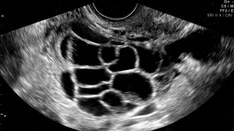

Chronic diarrhea can result from different mechanisms, such as motility disorders related to accelerated intestinal transit, malabsorption, osmotic diarrhea, and secretory diarrhea, which are often interlinked. When an endoscopy is performed, it is recommended to conduct multi-level biopsies to detect microscopic colitis, which Hammoudi believes is "probably underdiagnosed."

Hammoudi advised specialists seeking to determine the cause of chronic diarrhea to routinely collect multi-level bowel biopsies during colonoscopies from macroscopically normal mucosa to rule out microscopic colitis.